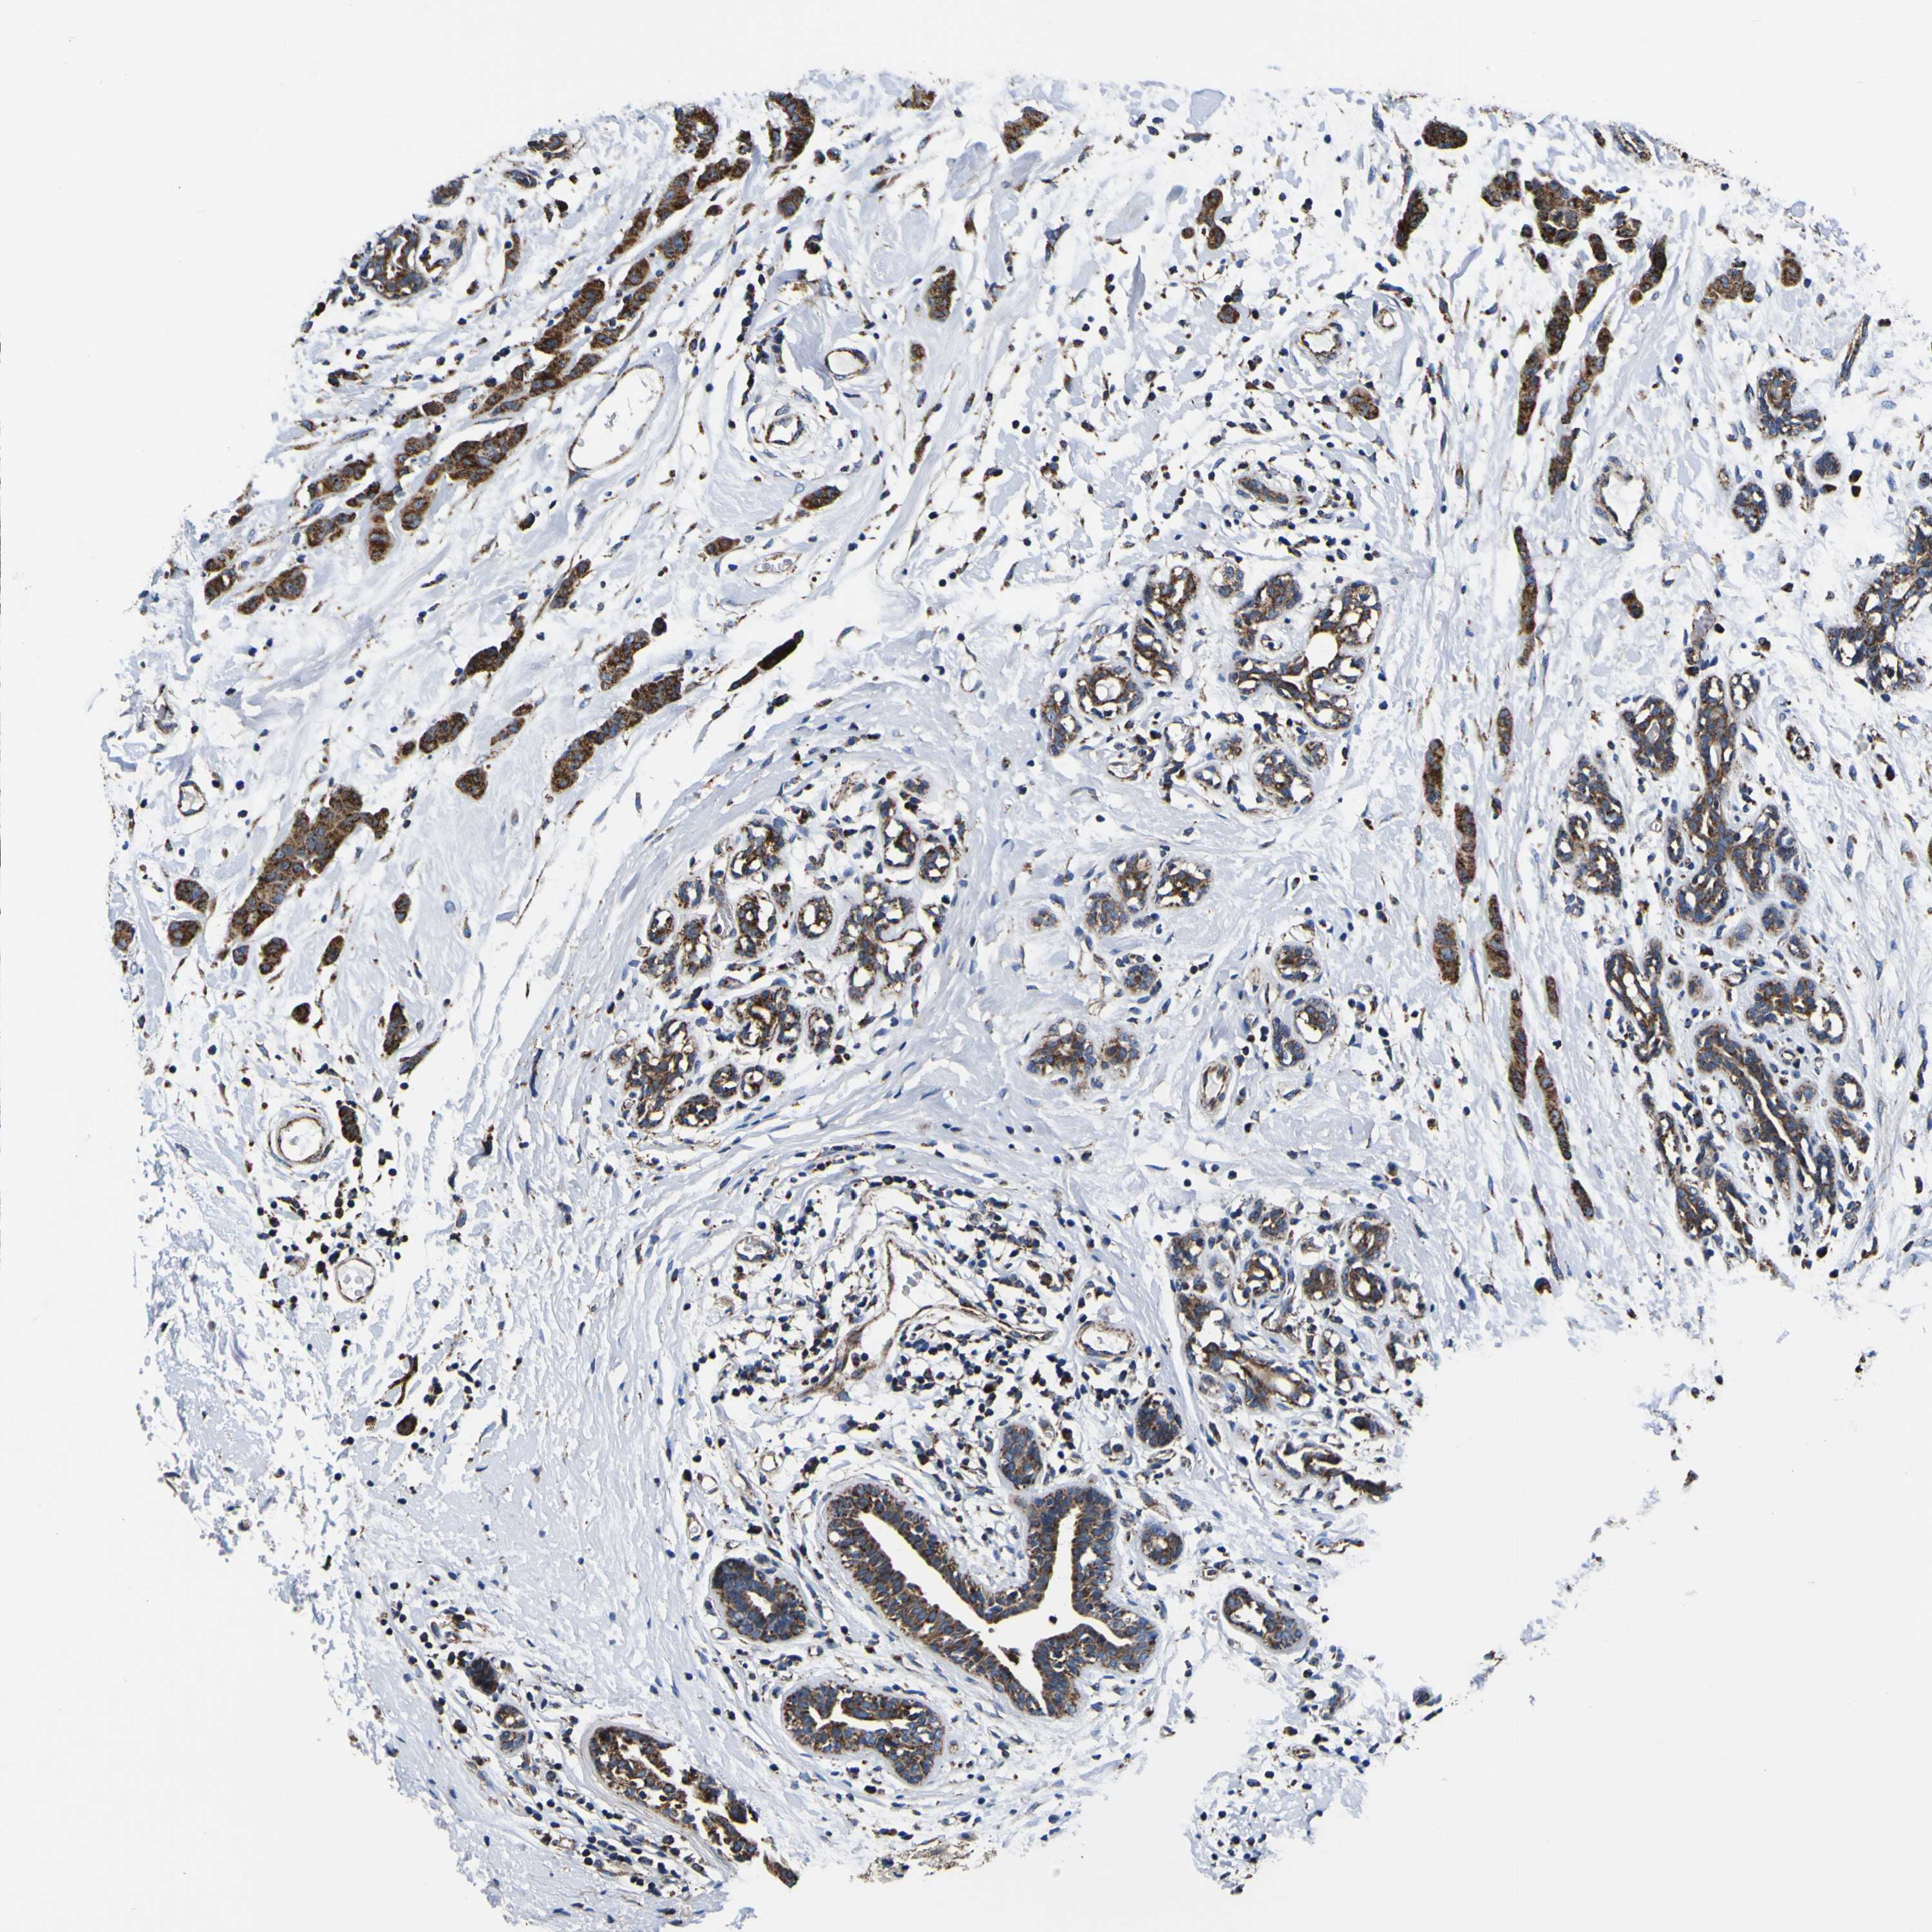

CANCER BREAST CANCER Show tissue menu

Breast cancer

Human cancer